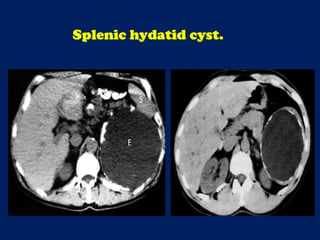

This document discusses imaging of the spleen and summarizes various congenital anomalies and pathologies that can affect the spleen. Some common congenital anomalies mentioned include accessory spleens, asplenia, polysplenia, and splenic fusions. Acquired conditions like repeated infarctions, infiltration, tumors, and cysts can also cause splenomegaly or functional asplenia. Wandering spleen is discussed as a rare congenital anomaly where the spleen lacks attachments and is mobile within the abdomen. Various grades of splenic lacerations and examples of splenic imaging findings are also briefly summarized.